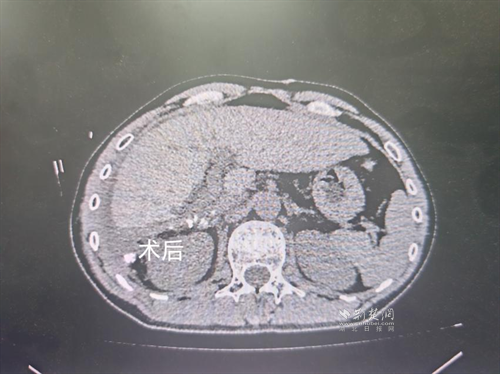

經(jīng)過肝膽外科牽頭組織的多學(xué)科MDT會(huì)診,團(tuán)隊(duì)確認(rèn)其適合接受當(dāng)前國(guó)際先進(jìn)的釔90樹脂微球選擇性內(nèi)放射治療。治療僅一個(gè)月后,患者病灶即從10cm縮小至6cm;術(shù)后六個(gè)月復(fù)查顯示,病灶體積進(jìn)一步縮小近40%,影像學(xué)檢查提示完全緩解,臨床分期成功轉(zhuǎn)化,達(dá)到手術(shù)切除標(biāo)準(zhǔn)。